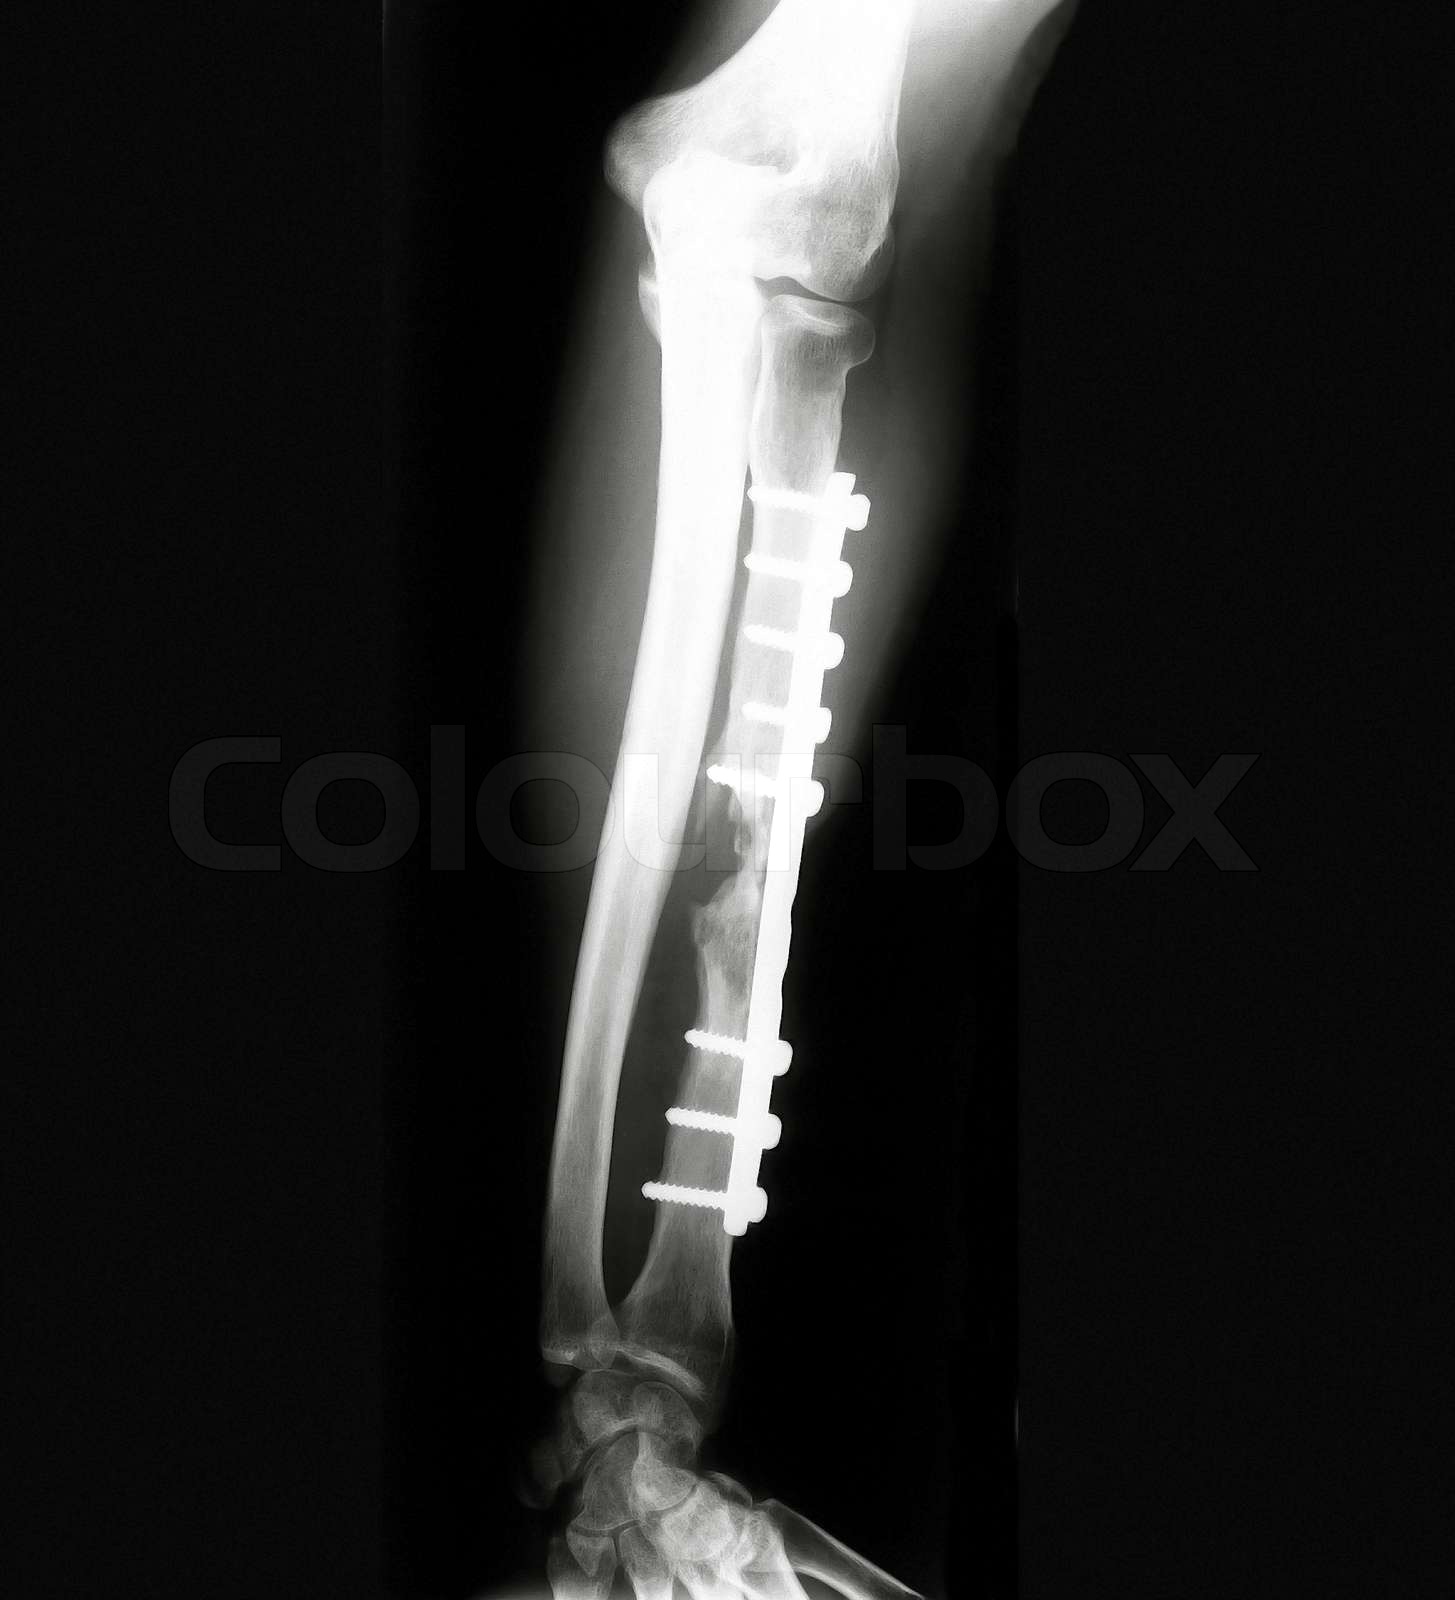

From www.colourbox.com

Xray of Forearm Stock image Colourbox Forearm X Ray Labeled Radius, ulna, carpals, distal humerus: This page contains radiographic anatomy of the adult forearm. However, its compartmental anatomy has not been widely reviewed in the radiology literature. Fractures, dislocations,and pathologic processes such as. Forearm fractures are characteristic depending on patient age. Typical fracture patterns arise in the forearm. Use the many eponyms with caution. The anatomy of the forearm is. Forearm X Ray Labeled.